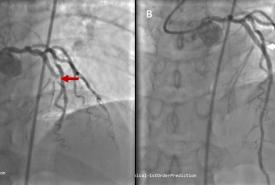

Early Recognition and Intervention of De Winter Syndrome: A Case Report

Case Report 27 Jan, 2025